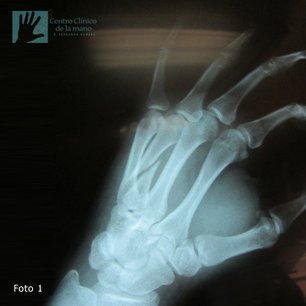

Fractura del Metacarpiano